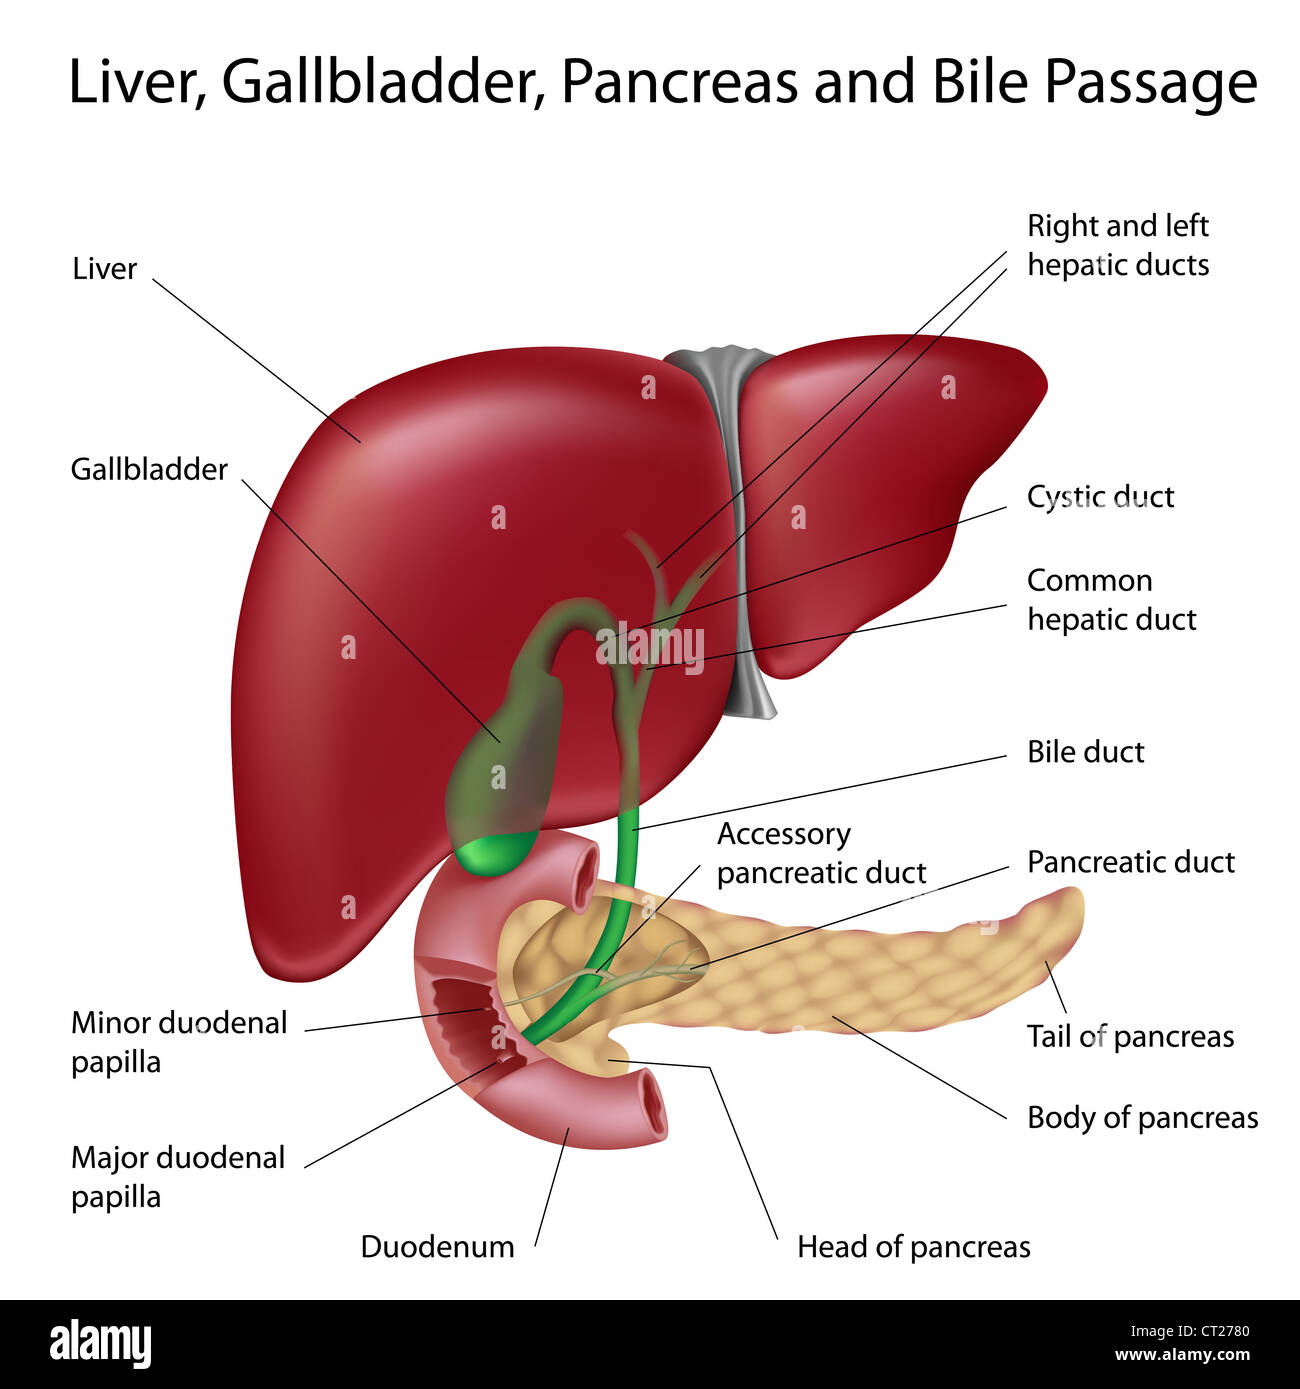

Bij een galwegontsteking (cholangitis) zijn de galwegen in of buiten de lever ontstoken. In de lever zitten veel kleine galkanaaltjes. Deze komen samen in de grotere galwegen. Via de grotere galwegen wordt de galvloeistof afgevoerd naar de galblaas en vervolgens naar de dunne darm. De galblaas.. Auszug. Die extra hepatischen Gallen wege in Form des Gallengangs und der Gallenblase garantieren den großen täglichen Bedarf an fettemulgierender Galle. Jede Unwegsamkeit darin provoziert ein Stenosemuster mit entsprechendem Gallenrückstau, der akut zum tödlichen Leberversagen und chronisch zu einem fibrodestruktiven Reaktionsmuster und.

Lever, galblaas en galwegen Algemene en abdominale heelkunde

De galblaas. Anatomie van de galblaas en galwegen. Anatomie van de twaalfvingerige darm en de

Anatomy of the gallbladder and bile ducts Surgery Oxford International Edition

Lever (Hepar)Galwegen en Galblaas